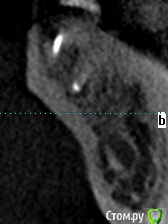

meld Опубликовано 7 ноября, 2017 Поделиться Опубликовано 7 ноября, 2017 Здравствуйте! Чуть больше года назад заболел 36 зуб. Я его пролечил с диагнозом периодонтит. 37 зуба нет. Было принято решение поставить мост с опорой на 36 и 38 зубы. 38 зуб был депульпирован в январе 2017 г. В мае 2017 я поставил мост. Вчера 38 зуб стал болеть при жевании. Боль не сильная, ломящая, через некоторое время проходит. Сегодня съездил в клинику, где лечил зубы, на осмотр. Осмотр ничего не выявил. Сделали прицельный снимок - по словам врачей (а их было двое) криминала тоже нет. Показал им свою томограмму - там тоже (по их словам) ничего нет. Посмотрите, пожалуйста, что не так. СпасибоСрезы 36 зуба Ссылка на комментарий